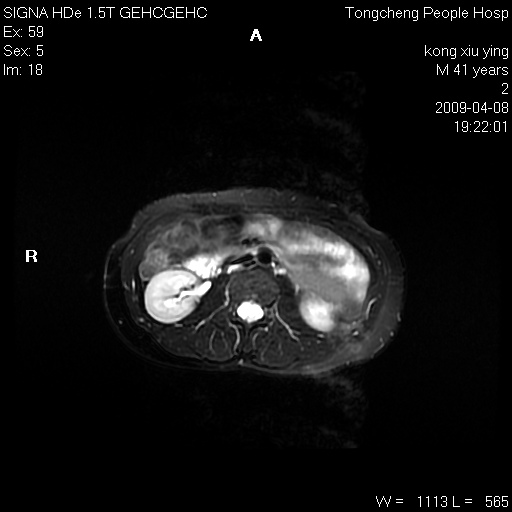

标题: CL1008:【经典】胆囊石榴籽样结石。

女,41岁。健康体检——彩超提示:胆囊显示不清。平素健康,无不适感。

腹部mr扫描及mrcp,图像如下: